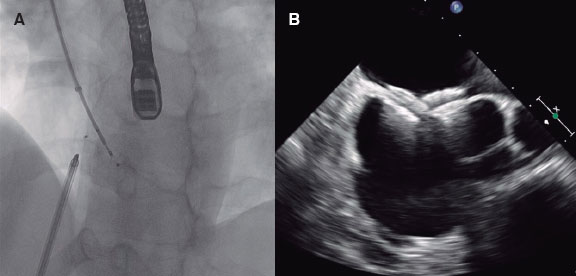

In moving towards a more personalized and precise provision of medical care, the convergence of intravascular imaging with computational processing and modeling will be a pivotal step to empower interventional cardiologists. The role and need for this convergence (figure 1), part of a wider vision of computational cardiology,2 is highlighted by several key challenges faced by the current interventional cardiology practice.

Figure 1. Our vision for the future of cardiovascular medicine is one in which physical and virtual medicine forms a continuum. Clinicians collect data including images and other test results from a patient. Anatomical and morphological information will be automatically extracted by algorithmic processing routines, distilled into reported quantitative metrics, and used to generate patient-specific computational models. Various simulated tests and procedures will be performed on the virtual patient. Results of the analyses and simulations will be transformed back into clinical data to enable a seamless integration and assessment by the heart team; the outcomes could inform the decision-making process and guide the patient's procedure.